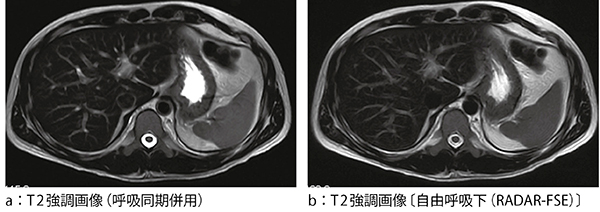

図5に,呼吸同期とRADARによる腹部の画像例を示す。RADARを用いることで,自由呼吸下においても同等の画質を得ることができている。また,図6に,Gd-EOB-DTPAを適用した臨床例におけるTIGRE息止め画像とRADAR-SE画像を示す。RADAR-SEでは自由呼吸下にて,より空間分解能の高い画質が得られている。

図5 呼吸同期とRADAR画像の比較